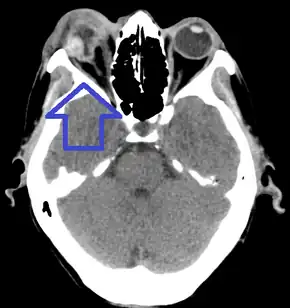

| Diagnostic method | Eye examination, CT scan[1] |

On CT scan, signs of global rupture include: deepening of the anterior chamber, alteration of global contour with scleral folds, discontinuity of scleral folds, and a shrunken globe.[6]

Globe rupture with protruding uveal tissue

Globe rupture with protruding uveal tissue